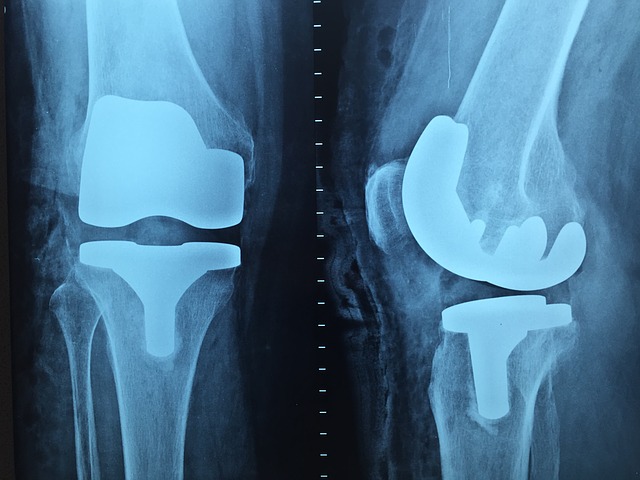

W sytuacjach związanych z trudnościami z poruszaniem się przydatna może być orteza kolana. Warto przeanalizować, kiedy zakłada się ortezę na kolano, a aby znaleźć odpowiednie dla siebie ortezy, należy wpisać w wyszukiwarkę odpowiednie hasła, jak np. „orteza kolana cena”.  Ortezy na staw kolanowy stosuje się po większości przebytych kontuzji i urazów. Również po takich, które wymagały leczenia operacyjnego. Dzięki takiej ortezie staw kolanowy może w bezpieczny sposób powrócić do pełnej sprawności. Ortezy kolana popularne są wśród sportowców z niemalże każdej dyscypliny sportu.

Ortezy na staw kolanowy stosuje się po większości przebytych kontuzji i urazów, również po takich, które wymagały leczenia operacyjnego. Pomaga ona stawowi kolanowemu bezpiecznie wrócić do pełnej sprawności.